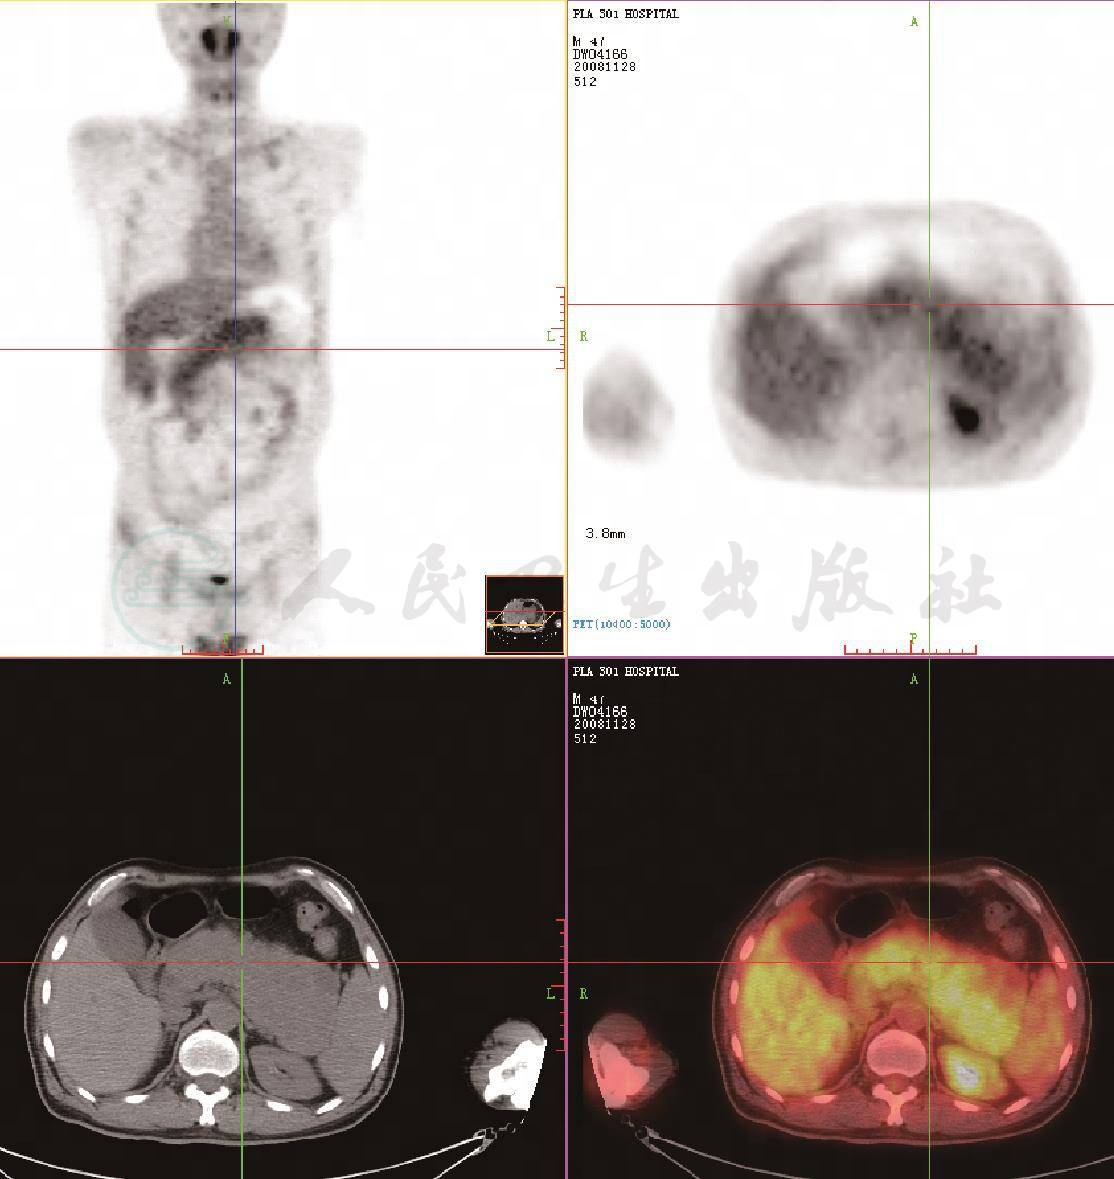

图1 PET/CT显像

胰腺弥漫肿大,CT值约36HU,胰体、尾尤著,最宽处超过6.7cm。胰腺呈弥漫性放射性摄取,SUVmax为3.7。胰尾部可见部分低密度区,局部放射摄取偏稀疏。胰管未见显著扩张

该患者18F-PET/CT主要表现为胰腺弥漫肿大,CT值约36HU,胰体、尾尤著,最宽处超过6.7cm,胰腺呈弥漫性放射性摄取,SUVmax为3.7。胰尾部可见部分低密度区,局部放射性摄取偏稀疏。胰管未见显著扩张。视野内轴心骨及上、下肢长骨骨髓见弥漫性放射性浓聚,放射性分布均匀,提示外周骨髓扩张。